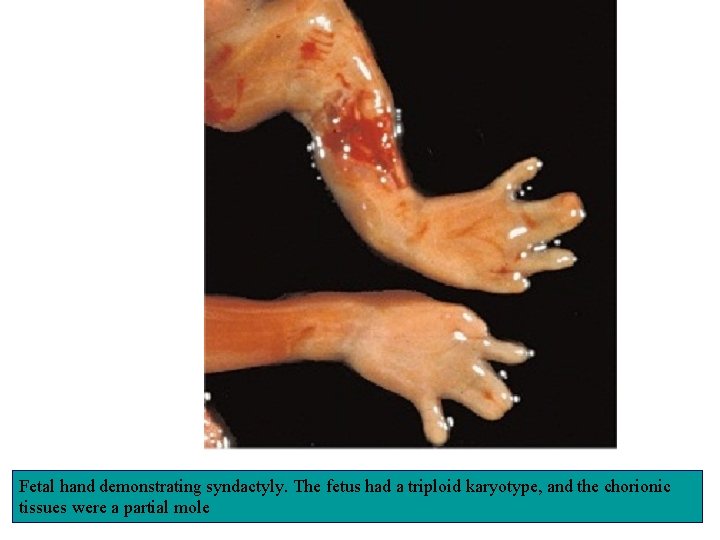

Fetal hand demonstrating syndactyly. The fetus had a triploid karyotype, and the chorionic tissues were a partial mole